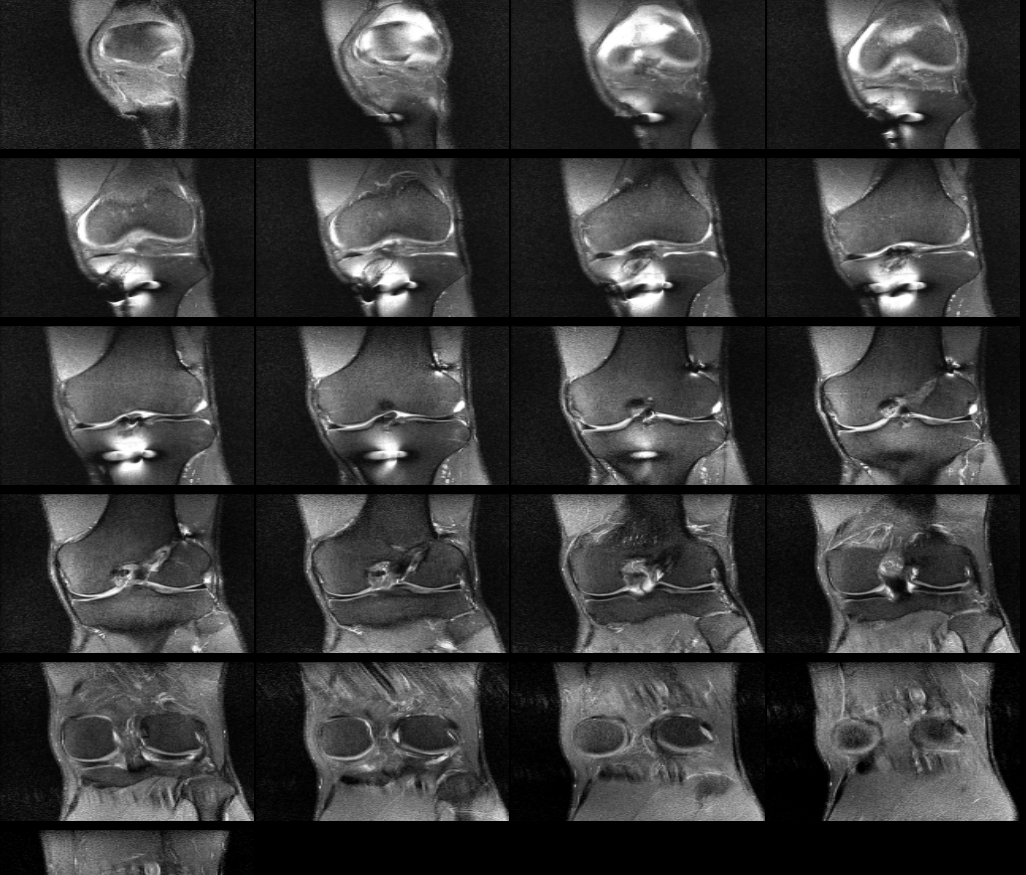

무릎 십자인대 재건술 후 약8년이 지난 지금 mri를 찍었습니다. 판독부탁드립니다ㅠㅠ

약 8년전 무릎 전방십자인대 재건술을 했는데 , 운동관련 직종이다 보니 , 운동을 많이 합니다.

최근들어 무릎에 불편한 통증이 있어 mri를 찍었는데 ,

활막염이라는 말만 들었는데 , 여러 선생님들의 의견을 듣고 싶어 사진올립니다. 판독해주시면 정말 너무너무

안녕하세요. 채홍석 의사입니다. MRI 퀄리티가 나빠서 판독은 어렵겠네요.